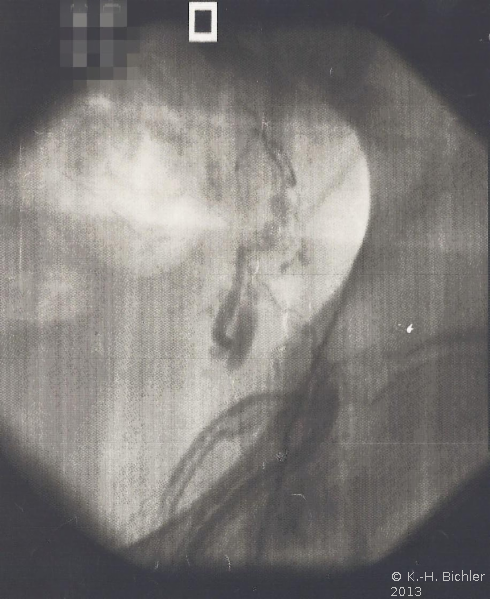

Phlebographie über eine Vene des Plexus pampiniformis. Nach Injektion von Kontrastmittel Darstellung mehrerer Kollateralen im Bereich der Beckengefäße, unter anderem zur Vena illiaca. Eine Sklerosierung wurde in Anbetracht der Kollateralen nicht durchgeführt (Abbildung HG1).